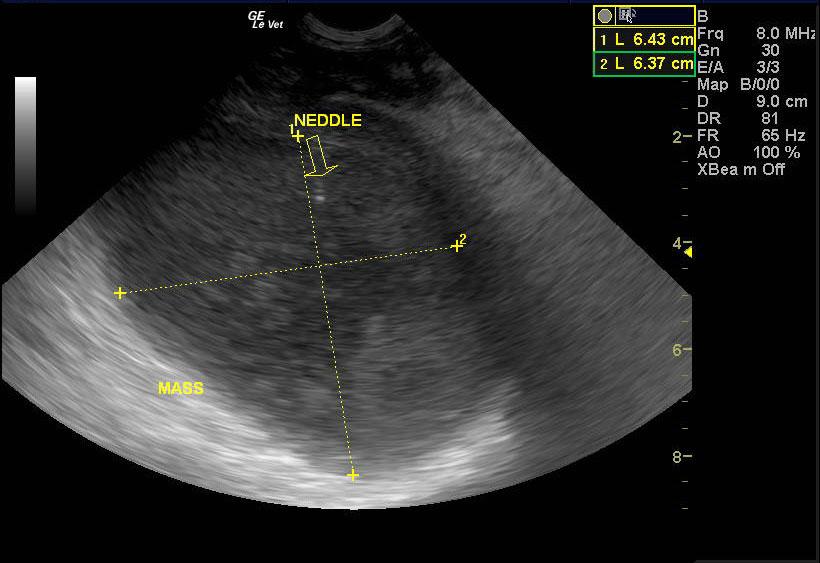

A 7 year old intact male pit bull terrier was presented for an abdominal tumor. Abnormalities on CBC and serum biochemistry were severe anemia and hypoalbuminemia.

A 7 year old intact male pit bull terrier was presented for an abdominal tumor. Abnormalities on CBC and serum biochemistry were severe anemia and hypoalbuminemia.